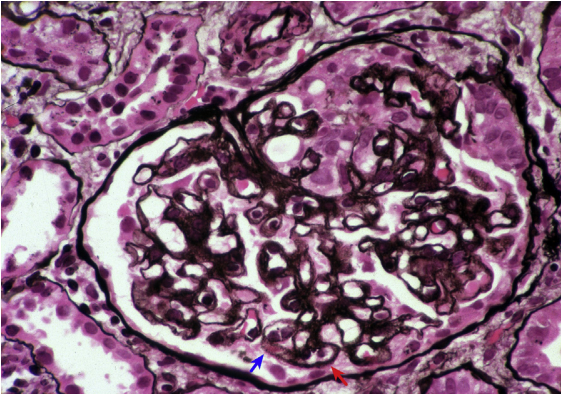

狼疮型肾炎Ⅴ型+Ⅲ型(膜性+局灶性LN),沿肾小球基底膜上有钉突(红色、蓝色箭头),双轨和早期新月体形成(银染)。